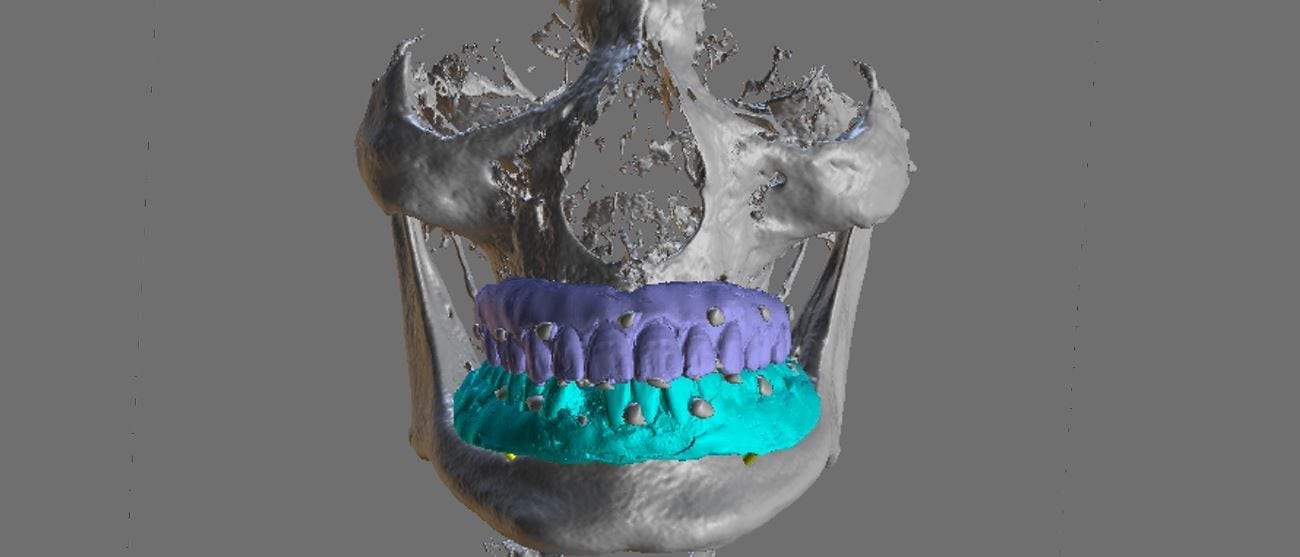

When planning for guided surgery in edentulous patients, it is important to have the final vertical dimension and tooth position determined. Ideally, a denture duplicate should be used with proper […]